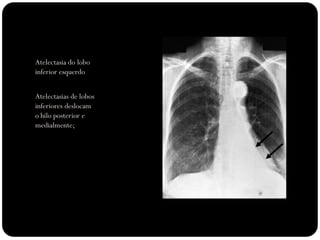

Atelectasia do lobo

inferior esquerdo

Atelectasias de lobos

inferiores deslocam

o hilo posterior e

medialmente;

 Atelectasia LIE:

 Opacidade triangular na área retrocardíaca

em incidência frontal;

 Fissura oblíqua deslocada mais

posteriormente e rodada em orientação

mais sagital do que a orientação coronal

normal;